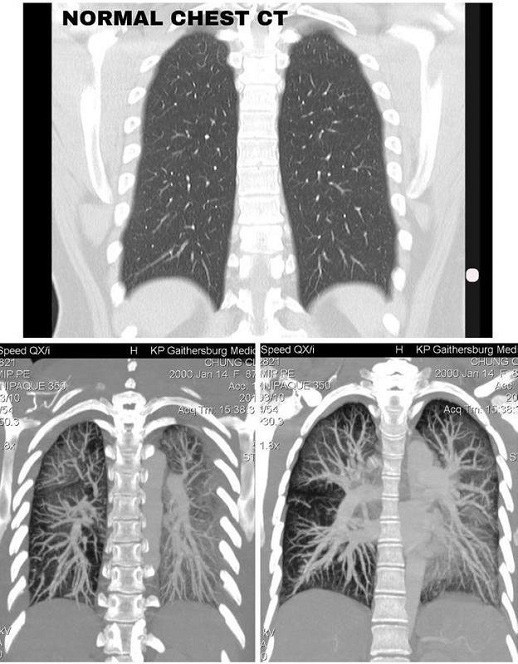

Trước đó, một cô gái tên Claire Chung (19 tuổi) sau khi chụp CT mới phát hiện hai lá phổi của mình đã đổi sang màu trắng đục. Trước đó cô từng làm bạn với khói thuốc điện tử.

Được biết, trước khi nhập viện Claire Chung bị sốt tới 40 độ C liên tục trong ba tuần liền. Tại bệnh viện các bác sĩ tiến hành chụp CT và kết luận phổi của cô gái 19 tuổi bị tổn thương nghiêm trọng. Trong ảnh chụp CT, hai lá phổi của BN có màu trắng đục (người bình thường chụp có màu đen).

Sau đó, trên trang cá nhân của mình, cô gái 19 tuổi Claire Chung đã đăng tải 1 bài viết kêu gọi mọi người bảo vệ sức khỏe: “Kết quả chụp CT phổi, vô cùng đáng lo. Phổi của người khỏe mạnh khi chụp CT sẽ có màu đen, còn tôi, ở tuổi 19, cả hai phổi toàn màu trắng đục.

Lá phổi của Claire qua hình ảnh CT.